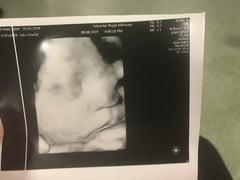

Megan2018 · 08/08/2019 16:36

Growth scan done, 35 weeks and estimated weight today 5lb 3. We have dropped slightly on the chart so no indication this GD baby is going to be big! Back again in just over 2 weeks for another one. Oh, and as it was a research scan with the Fetal Medicine consultant got a free 3D photo! 😍🤗

Florencenotflo · 08/08/2019 16:40

How cool is that @Megan2018!

Who does he/she look like most?

Omg megan look at her pudgy face! ❤

Aww @megan2018 so cute!

Aw, @Megan2018 too cute!!

Lovely 3d photo Megan great weight with little chubby cheeks.

@Megan2018 your scan pic is gorgeous but just in case you hadn't noticed your name is visible.

@Florencenotflo I think she looks like my DH, but hard to tell as so squished! I must admit I did almost cry when saw it, was unexpected and makes it so real!

@Megan2018 v cute picture!!